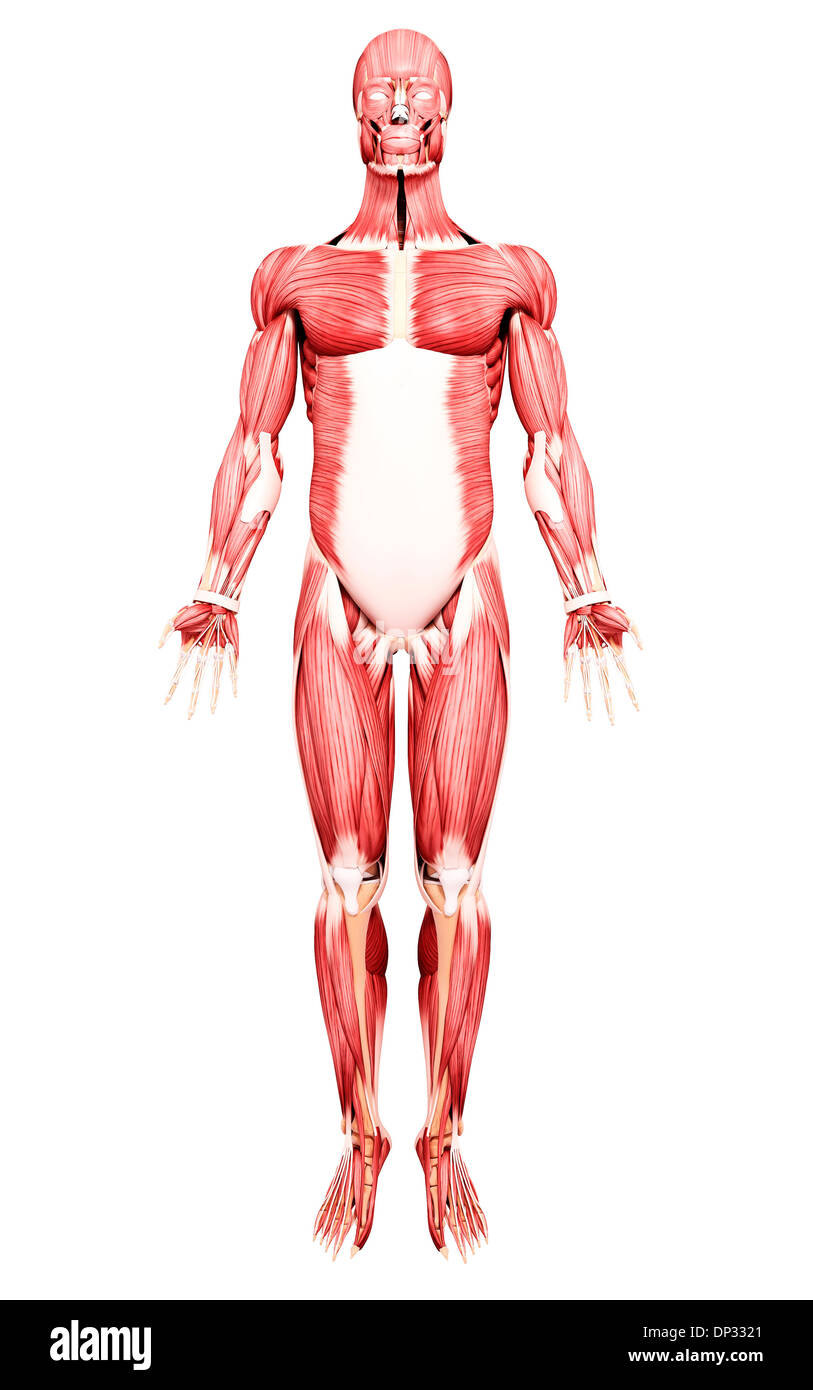

Human Anatomy, artwork Banque D'Imageshttps://www.alamyimages.fr/image-license-details/?v=1https://www.alamyimages.fr/human-anatomy-artwork-image65242387.html

Human Anatomy, artwork Banque D'Imageshttps://www.alamyimages.fr/image-license-details/?v=1https://www.alamyimages.fr/human-anatomy-artwork-image65242387.htmlRFDP4197–Human Anatomy, artwork